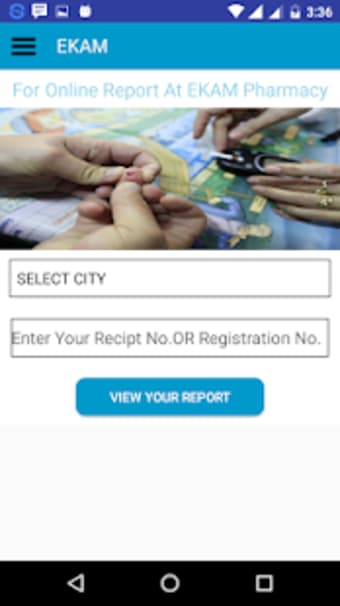

Бесплатная программа для Android от Gayatri Softwares.

Ekam– это бесплатное приложение для Android, относящееся к категории "Медицина".

Ekam требует Android 9.0 или выше. Текущая версия программного обеспечения — 1.0, и вы можете получить ее только на английском языке.